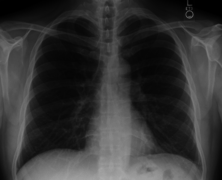

In radiology, a chest radiograph, colloquially called a chest X-ray (CXR), or chest film, is a projection radiograph of the chest used to diagnose conditions affecting the chest, its contents, and nearby structures. Chest radiographs are the most common film taken in medicine.

Chest X-ray PA